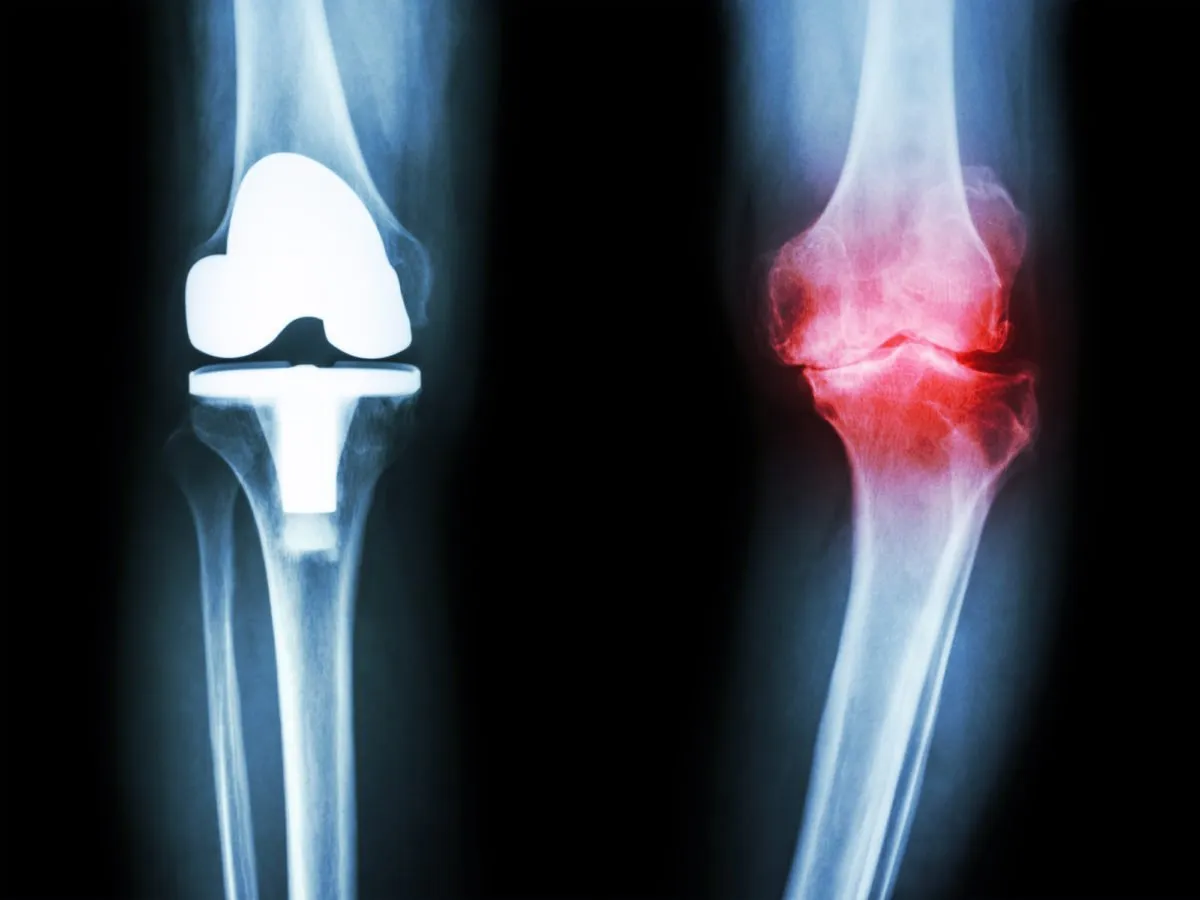

- اشعه ایکس: کاهش فاصله بین استخوانها، زوائد استخوانی و تغییر شکل مفصل را نشان میدهد.

- آرتروسکوپی: پاکسازی مفصل از زوائد استخوانی و غضروفی.

- تعویض مفصل: در موارد شدید، مفصل آسیبدیده با پروتز جایگزین میشود.